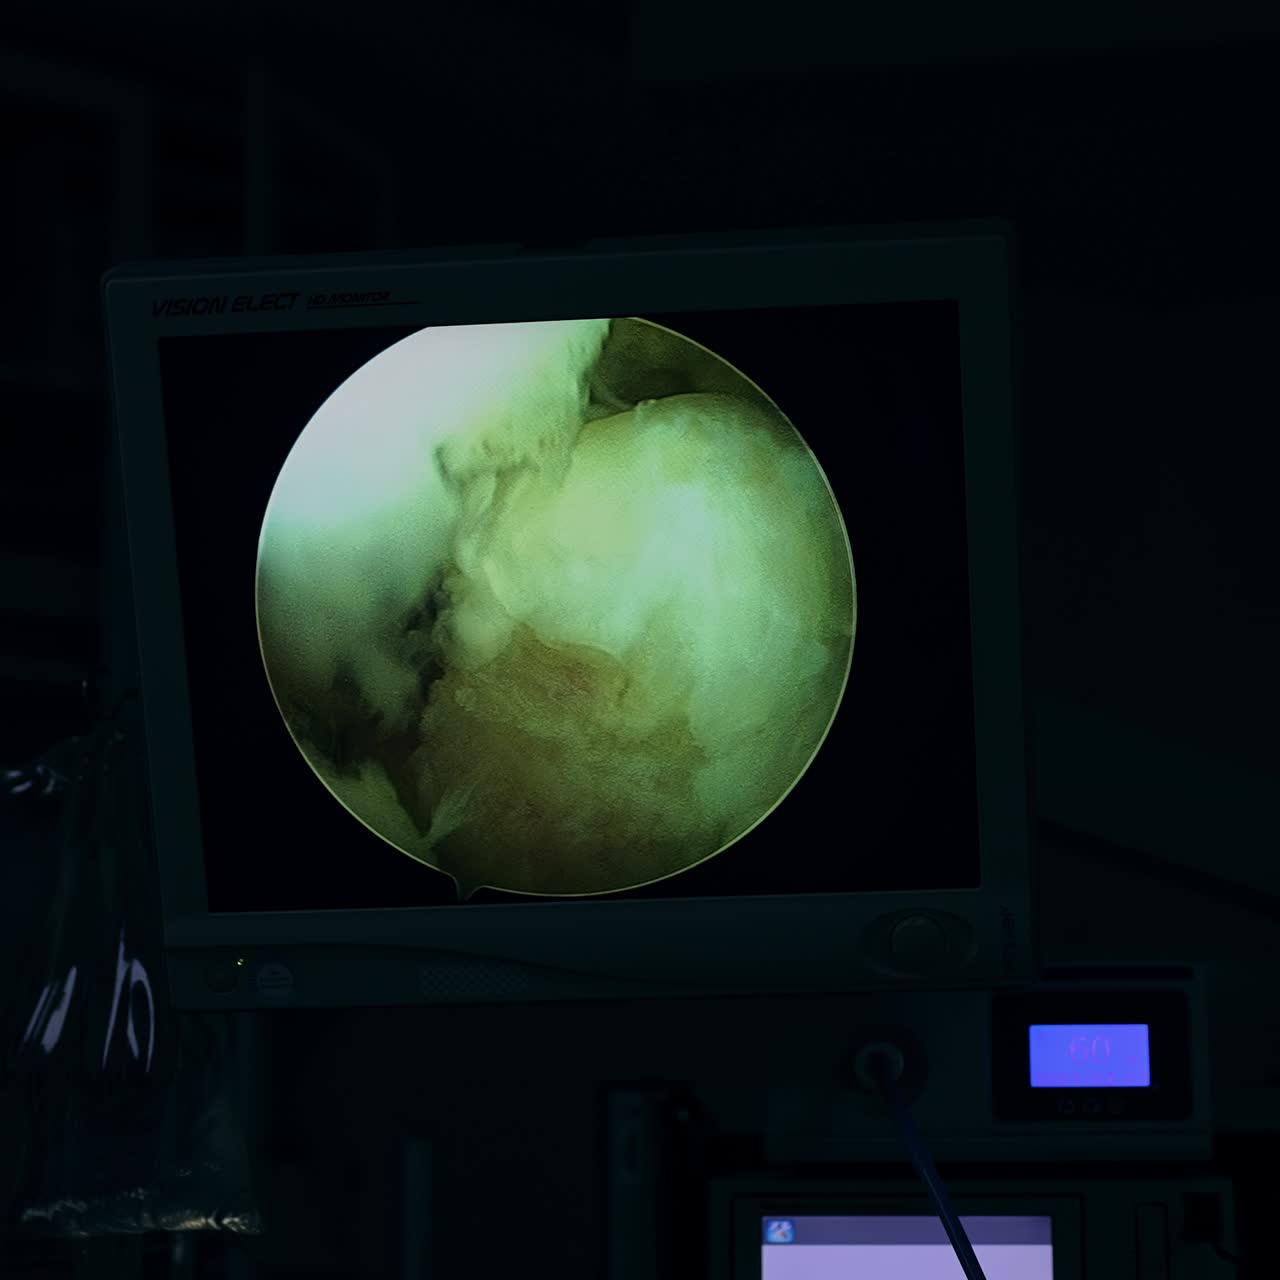

램프 모니터 비디오

- 24 페이지